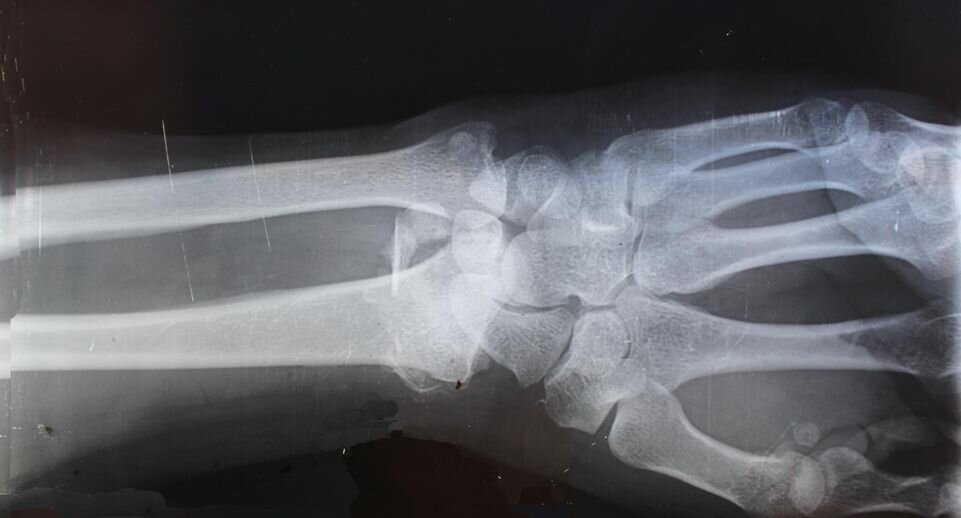

Пациент 40 лет поступил в больницу Жуковского с болезненным отеком левой руки. Пару дней назад он прищемил кисть дверью, и она стала увеличиваться в объеме. Со временем боль набрала силу и снять ее лекарствами уже не получалось. Мужчина обратился за медицинской помощью.

Врачи провели обследование и выявили у пациента острое гнойное воспаление левой кисти и предплечья. Ситуация осложнялась начавшимся сепсисом. Стремительное развитие инфекции спровоцировал сахарный диабет, о котором мужчина не знал. Его экстренно отправили в отделение гнойной медицины, где врачи выполнили сложную операцию по спасению руки. Рану вскрыли от кисти до локтя.

«Было проведено три операции. Сначала мы вскрыли гнойное воспаление, затем рассекли омертвевшие ткани и обследовали послеоперационную рану. В конце ушили ткани. Из-за того что у пациента не хватало собственной кожи, воспользовались подкожной жировой тканью. Руку удалось спасти», — рассказал врач-хирург отделения гнойной хирургии Анна Маркова.

На данный момент пациент чувствует себя хорошо и уже выписан на амбулаторное лечение. Врачи дали ему рекомендации по питанию в связи с выявленным сахарным диабетом.